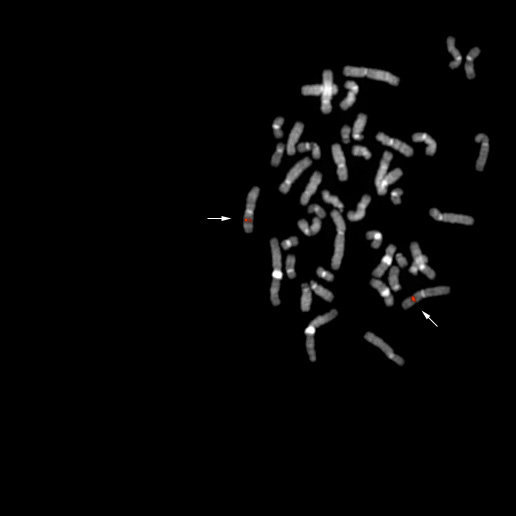

bA89F17